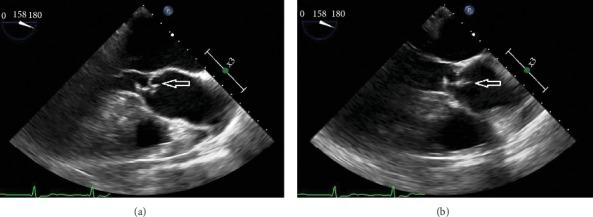

is a beta-hemolytic Gram-positive, catalase-negative, nonmotile coccus arranged in short chains, usually found in the female genitourinary tract and differentiated from in 2006. Only two human infections associated with this organism have been reported to date: one in a patient with a first digit wound infection and another with lower extremity cellulitis. We describe two novel cases of causing endocarditis in one and pneumonia with empyema in another, illustrating the potential of these bacteria to cause severe invasive and life-threatening disease.

是一种β溶血性革兰氏阳性、过氧化氢酶阴性、无动力的球菌,呈短链排列,通常存在于女性泌尿生殖道,于2006年与[未提及的菌]区分开来。迄今为止,仅报告了两例与该菌相关的人类感染病例:一例是手指伤口感染患者,另一例是下肢蜂窝织炎患者。我们描述了两例新病例,一例由[该菌]引起心内膜炎,另一例引起肺炎伴脓胸,说明了这些细菌引发严重侵袭性和危及生命疾病的可能性。